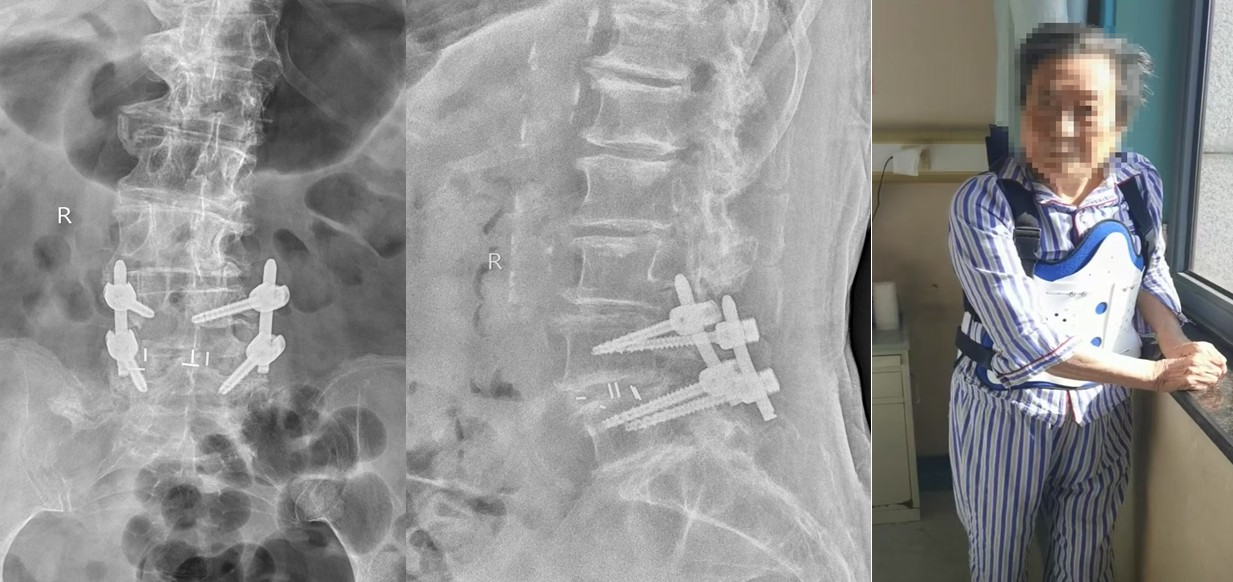

运动医学与小儿骨科病区柏传毅教授团队成功为一位92岁的腰椎滑脱、腰椎间盘突出合并腰椎管狭窄、退变性侧凸患者实施了微创小通道下减压固定融合手术,术后患者疼痛迅速减轻,术后5天下地行走及活动,老人重新过上了久违的正常生活。

患者入院后经过全面的检查和多学科会诊,积极术前准备,柏传毅教授和党晓谦主任、时志斌主任讨论后决定采用全麻脊柱微创通道下为患者行椎间盘髓核摘除,椎管扩大,融合器植入椎弓根固定手术,使患者尽早恢复下地行走及日常活动,减少卧床引起诸多的并发症。11月15日在麻醉科张晓琴教授麻醉后,使用脊柱微创通道完成了髓核摘除椎管减压固定手术,顺利完成。术后5天患者下地活动,疼痛明显减轻,患者逐渐恢复正常生活。